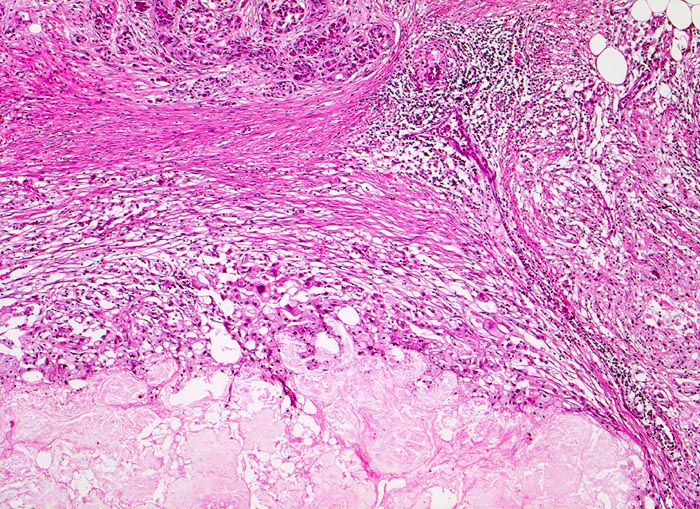

PathoPic – image database / PathoPic ID 4668 - Chronisch-sklerosierende Pankreatitis mit älterer Nekrose

Chronisch-sklerosierende Pankreatitis mit älterer Nekrose

Anschnitt eines fibrosierten Läppchens. Daran angrenzend eine breite Sklerosezone mit lockerem chronischem Entzündungsinfiltrat. Unten im Bild eine alte, lytische Gewebsnekrose als Überbleibsel eines akuten Pankreatitisschubes.

Alkoholiker mit rezidivierten akuten Pankreatitisschüben. Chronische Diarrhoe.

Die chronische Pankreatitis bei Alkoholikern verläuft meist schubweise.